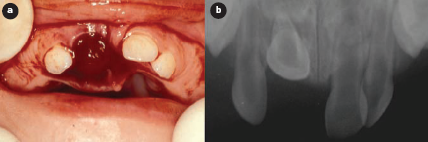

L'examen intrabuccal a révélé la présence d'un caillot de sang dans la région alvéolaire de l'incisive centrale supérieure droite primaire (dent 51), ainsi qu'une importante lacération de la muqueuse palatine (ill. 1a). À la palpation, une surface durcie a été perçue dans la région linguale. L'examen radiographique (ill. 1b) a révélé une intrusion marquée de la dent 51 avec luxation linguale.

Ill. 1 : Premier examen : a) vue clinique de la zone atteinte; b) aspect radiologique de la dent enfoncée.